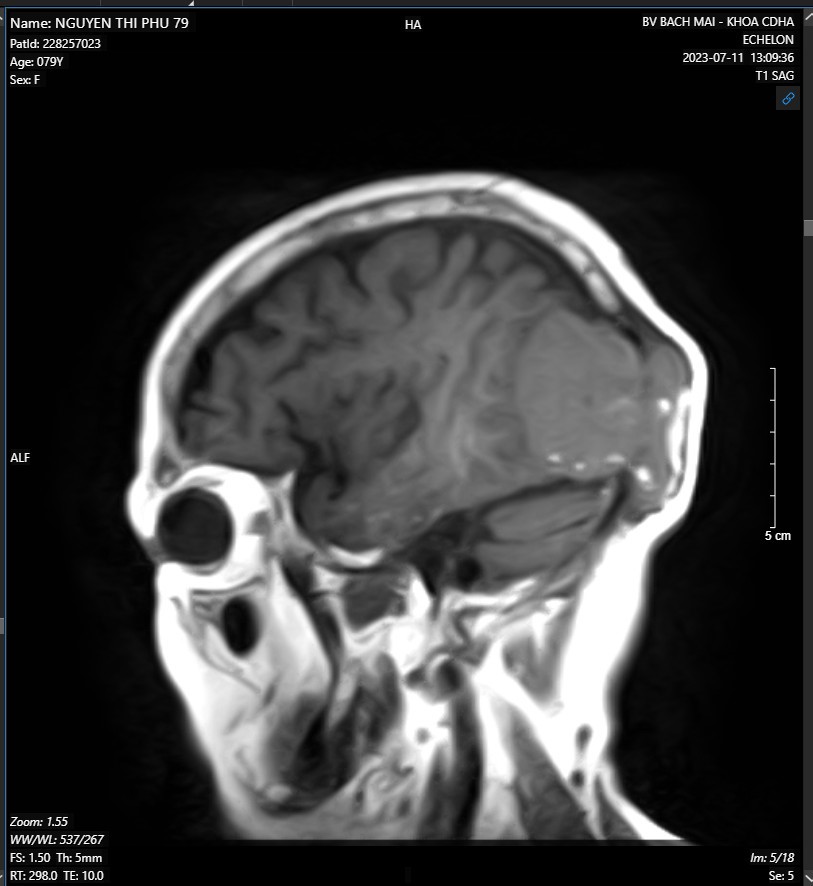

- MRI não-mạch não có tiêm thuốc đối quang từ:

Hình ảnh khối ngoài trục vùng thái dương-chẩm phải kích thước 48x50x60mm nghĩ nhiều đến khối u xương, có chảy máu trong u, gây tiêu xương sọ và xâm lấn phần mềm

Hình 2. Hình ảnh MRI não-mạch não có tiêm thuốc đối quang từ.